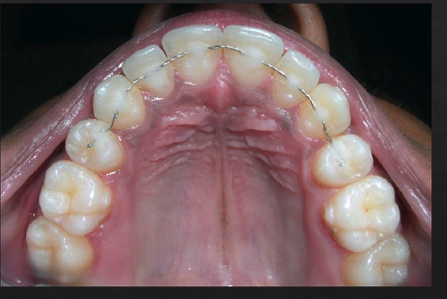

splinting of teeth

what are some indications for splinting teeth?

For patient comfort on mobile teeth

Pathologic tooth migration

Guided tissue regeneration on mobile teeth

Prosthetics where multiple abutments needed

what is a prerequisite to splinting?

control of periodontal inflammation

t/f: splinting itself induces periodontal regeneration

false. Splinting only mechanically stabilizes teeth, it does NOT by itself induce periodontal regeneration